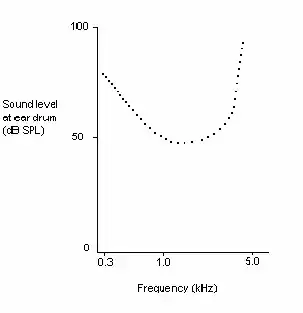

Dead regions affect audiometric results, but perhaps not in the way expected. For example, it may be expected that thresholds would not be obtained at the frequencies within the dead region, but would be obtained at frequencies adjacent to the dead region. Therefore, assuming normal hearing exists around the dead region, it would produce an audiogram that has a dramatically steep slope between the frequency where a threshold is obtained, and the frequency where a threshold cannot be obtained due to the dead region.[15]

However, it appears that this is not the case. Dead regions cannot be clearly found via PTA audiograms. This may be because although the neurons innervating the dead region, cannot react to vibration at their characteristic frequency. If the basilar membrane vibration is large enough, neurons tuned to different characteristic frequencies such as those adjacent to the dead region, will be stimulated due to the spread of excitation. Therefore, a response from the patient at the test frequency will be obtained. This is referred to as “off-place listening”, and is also known as ‘off-frequency listening’. This will lead to a false threshold being found. Thus, it appears a person has better hearing than they actually do, resulting in a dead region being missed. Therefore, using PTA alone, it is impossible to identify the extent of a dead region (See Figure 7 and 8).[15]

Consequently, how much is an audiometric threshold affected by a tone with its frequency within a dead region? This depends on the location of the dead region. Thresholds at low frequency dead regions, are more inaccurate than those at higher frequency dead regions. This has been attributed to the fact that excitation due to vibration of the basilar membrane spreads upwards from the apical regions of the basilar membrane, more than excitation spreads downwards from higher frequency basal regions of the cochlea. This pattern of the spread of excitation is similar to the ‘upward spread of masking’ phenomenon. If the tone is sufficiently loud to produce enough excitation at the normally functioning area of the cochlea, so that it is above that areas threshold. The tone will be detected, due to off-frequency listening which results in a misleading threshold.[15]

To help to overcome the issue of PTA producing inaccurate thresholds within dead regions, masking of the area beyond the dead region that is being stimulated can be used. This means that the threshold of the responding area is sufficiently raised, so that it cannot detect the spread of excitation from the tone. This technique has led to the suggestion that a low frequency dead region may be related to a loss of 40-50 dB.[16][17] However, as one of the aims of PTA is to determine whether or not there is a dead region, it may be difficult to assess which frequencies to mask without the use of other tests.[15]

Based on research it has been suggested that a low frequency dead region may produce a relatively flat loss, or a very gradually sloping loss towards the higher frequencies. As the dead region will be less detectable due to the upward spread of excitation. Whereas, there may be a more obvious steeply sloping loss at high frequencies for a high frequency dead region. Although it is likely that the slope represents the less pronounced downward spread of excitation, rather than accurate thresholds for those frequencies with non-functioning hair cells. Mid-frequency dead regions, with a small range, appear to have less effect on the patient's ability to hear in everyday life, and may produce a notch in the PTA thresholds.[15] Although it is clear that PTA is not the best test to identify a dead region.[18]